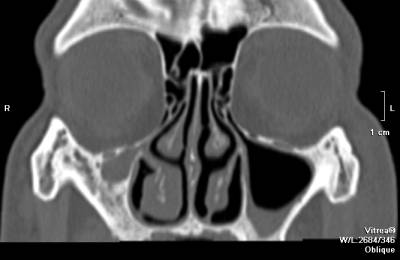

Кроме того выполняется рентгенологическое исследование – рентген придаточных носовых пазух.

При этом в полостях практически всегда определяется уровень жидкости. Для подтверждения диагноза также можно выполнить компьютерную томографию. Однако это довольно дорогостоящий метод, который не всегда дает больше информации, чем рентген.

По этой причине компьютерную томографию не назначают всем пациентам. Этот метод используют лишь в тех случаях, когда рентгенологическое исследование является малоинформативным. Важной является диагностическая пункция носовых пазух, которая позволяет определить наличие гноя в полости.

- определение уровня гноя или крови при проведении диагностики – по данным компьютерно-томографического или рентгенологического исследования;